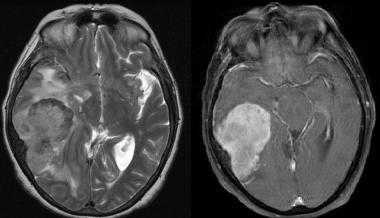

(Слева) Злокачественная менингиома, инфильтрирующая кожу волосистой части головы, череп и смежные отделы головного мозга. Протяженной вазогенный отек изображен серым цветом. Обратите внимание на остеолизис, инвазию твердой/паутинной мозговой оболочки, «грибовидную» форму опухоли и ее «вплетение» в головной мозг.

(Справа) МРТ, постконтрастное Т1 -ВИ, сагиттальный срез: злокачественная менингиома, накапливающая контрастное вещество, и вовлекающая в процесс кожу головы, череп и смежные отделы головного мозга. Обратите внимание на «грибовидное» прорастание опухоли через твердую мозговую оболочку, выраженный гипоинтенсивный отек мозговой ткани. (Слева) МРТ, Т2-ВИ, аксиальный срез: у мужчины 71 года визуализируется объемное образование с четкими контурами, прилежащее широким основанием к твердой мозговой оболочке по ходу большого крыла клиновидной кости. Объемное образование изоинтенсивно по отношению к коре, отчетливо визуализируется ликворная щель, признаков локальной инвазии мозгвой ткани не отмечается.

(Справа) МРТ, постконтрастное Т1-ВИ, режим подавления сигнала от жира, аксиальный срез: интенсивное равномерное контрастное усиление. При операции признаков инвазии смежной мозговой паренхимы выявлено не было. При патоморфологическом исследовании была диагностирована менингиома grade II.